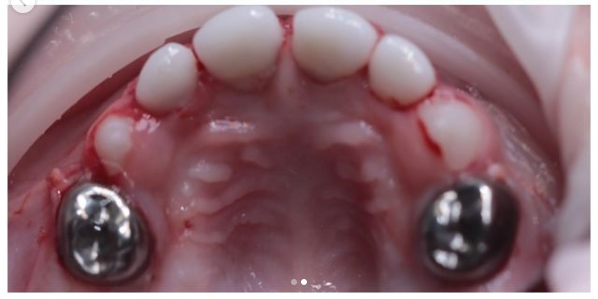

Бутина Елена Александровна: портфолио (8)